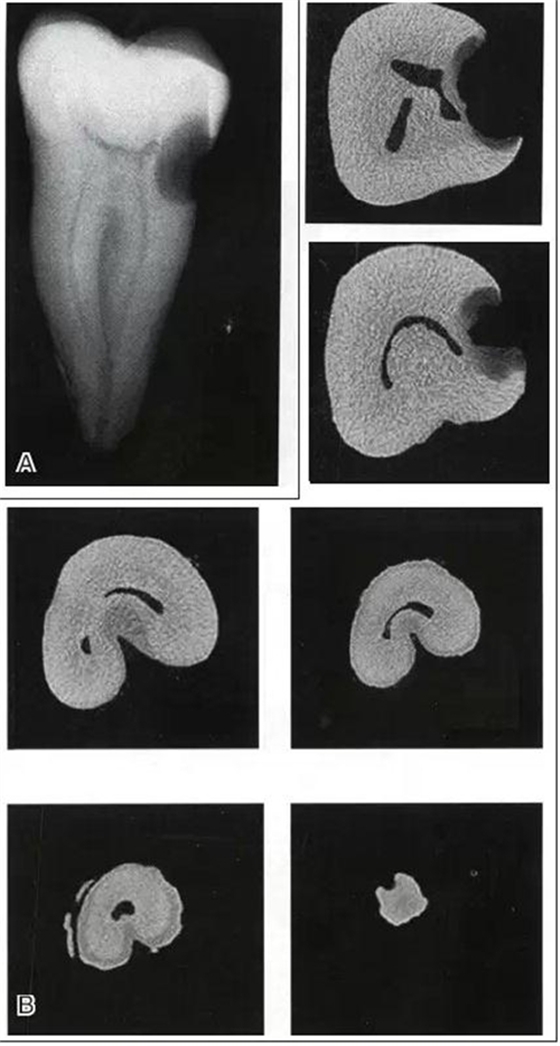

與傳統(tǒng)根管形態(tài)概念不同,C形根管形態(tài)從根管口到根尖有很大變異(圖1)。有些斷面呈C形,有些又呈分號形,有些斷面僅呈點狀。

圖1 下頜第二磨牙C形根管系統(tǒng)的形態(tài)從根管口到根尖(A~H)可發(fā)生巨大變化